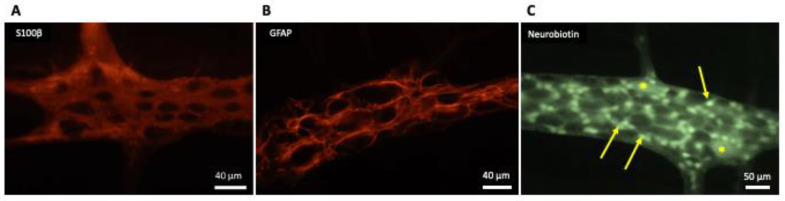

Generally, EGCs are considered as non-excitable cells, as they are unable to generate an action potential. Furthermore, EGCs are interconnected and electrically coupled by gap junctions that form an extensive glial network [ref. 9], as shown in Figure 1.

Enteric glial cells communicate with surrounding cells (neurons, glia, epithelial cells, immune cells) and integrate received information through calcium signaling [ref. 10]. Intercellular communication is a result of the propagation of calcium waves through connexin 43 (Cx43) hemichannels [ref. 11]. Moreover, EGCs are susceptible to the activation by neural pathways: intrinsic (from enteric neurons) or extrinsic (from autonomic or primary afferent neurons). The major neurotransmitter involved in this extracellular signaling is adenosine triphosphate (ATP) [ref. 12]. It was found that intermuscular EGCs express the purinergic receptor (P2X7) [ref. 13].